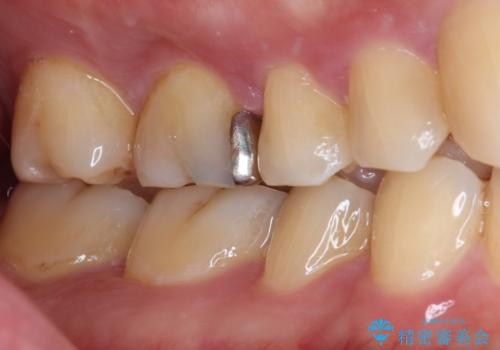

- 保険診療で治療した銀歯のやり替え希望の患者様です。

銀歯とその下の虫歯を除去し、形を整え、精度の良いシリコーンによる型どりを行いました。

セラミックインレーを接着する際は、ラバーダム防湿を行いました。